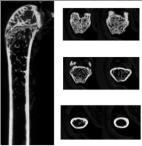

拍照部位要求 | 例:冠状位+横断位 2、6周骨折线及金属针要拍出来,12周骨折线因愈合可能消失 | ||||||

皮质骨 | 皮质骨总面积 | Tt.Ar | mm2 | ||||

皮质骨面积 | Ct.Ar | mm2 | |||||

皮质骨厚度 | Ct.Th | μm | |||||

皮质骨面积与总面积的比值 | Ct.Ar/ Tt.Ar | % | |||||

骨髓腔面积 | Ma.Ar | mm2 | |||||

皮质骨参数 | 皮质骨总面积(Tt.Ar) | 皮质骨面积(Ct.Ar) | 皮质骨厚度(Ct.Th) |

皮质骨面积与总面积比值(Ct.Ar/ Tt.Ar) | 骨体积(Ct.BV) | 组织矿物质含量(Ct.TMC) | |

组织矿物质密度(Ct.TMD) | 骨髓腔区域面积(Ma.Ar) | ||